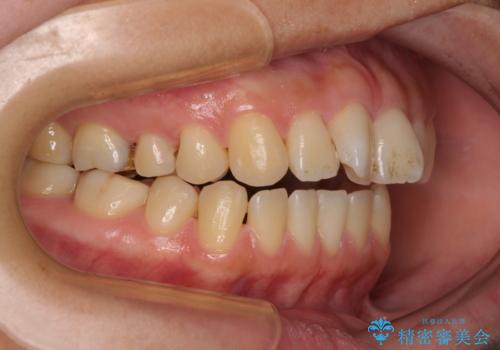

- 下顎小臼歯が欠損しており、さらに上顎が全体的に突出していることを気にして来院された患者様です。

下顎は片方の小臼歯が欠損していたため、正中がずれた上に、上下前歯が接触していない状態でした。

上顎左右の小臼歯2本および下顎小臼歯を1本抜歯し、補助装置を用いて上顎大臼歯が前方に移動しないように固定した上で、ワイヤー装置にて矯正治療を行うこととしました。

上下前歯のズレは舌の突出癖による影響も大きいと考えられたたため、舌のトレーニングをしっかりと行っていただきました。